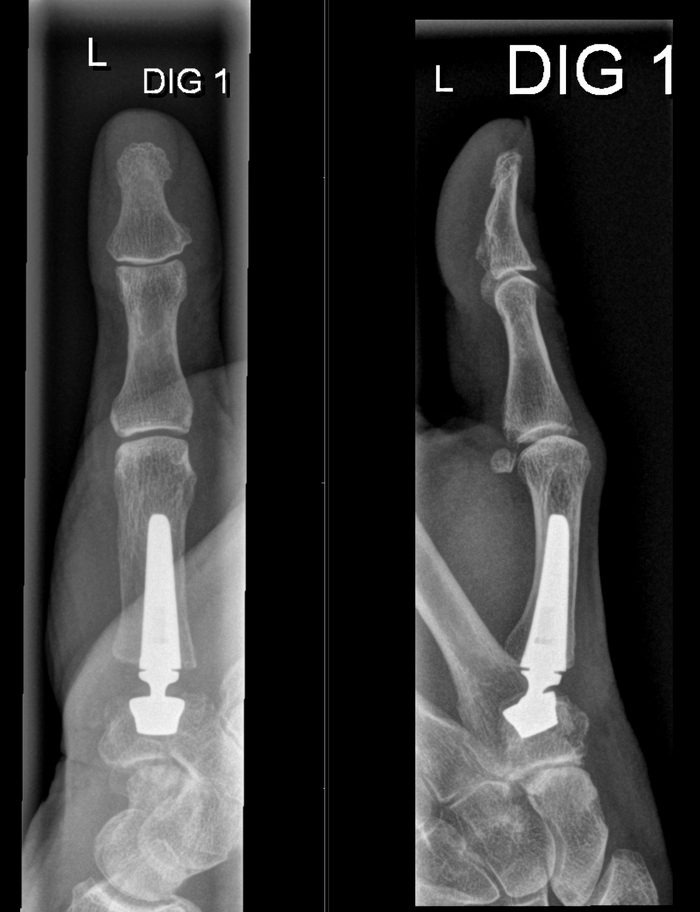

Сегодня будет пара слов, а точнее пара картинок, посвящённых всяким разным протезам, а они, как вы увидите, бывают разные. Я не буду здесь писать о показаниях к протезированию, т.к. это не мой хлеб и этим занимаются уважаемые коллеги из травматологии-ортопедии, а просто покажу изображения для общего представления о современных возможностях и, если возникнут вопросы - милости прощу в комментарии.

Все представленные снимки из учреждения, где я работаю. Собирал эту небольшую коллекцию около 9 месяцев, так как некоторые протезы встречаются не часто.

Начнём с нижних конечностей, где импланируют протезы:

- первого карпометакарпального сустава

- межфалангового сустава (здесь уже нередко не металл, но синтетические материалы)